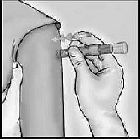

Bağışıklama, intradermal yoldan yapılmalıdır. Tavsiye olunan enjeksiyon yeri deltoid bölgesidir. Hazırlanmasına ilişkin daha detaylı talimatlar için Bölüm 6.6’ya bakınız. Kullanıma hazır enjektörün kullanılışı:

Deri içi (intradermal) enjeksiyon için Mikro-Enjeksiyon Sistemi, bir mikro iğne (1,5 mm) ile bir iğne muhafaza sistemine sahip kullanıma hazır bir enjektörden oluşur.

UYGULAMA TALİMATLARI Kullanmadan önce aşağıdaki talimatları lütfen okuyun

1-İĞNE BAŞLIĞINI ÇIKARTIN

İğne başlığını Mikro-Enjeksiyon Sisteminden çıkartın.

İğne yoluyla dışarıya hava boşaltmayın.

3-İĞNEYİ DERİYE DİK BİR AÇIYLA HIZLI BİR ŞEKİLDE SOKUN

İğneyi deltoid bölgesindeki deriye dik bir açıyla kısa ve hızlı bir hareketle saplayın.